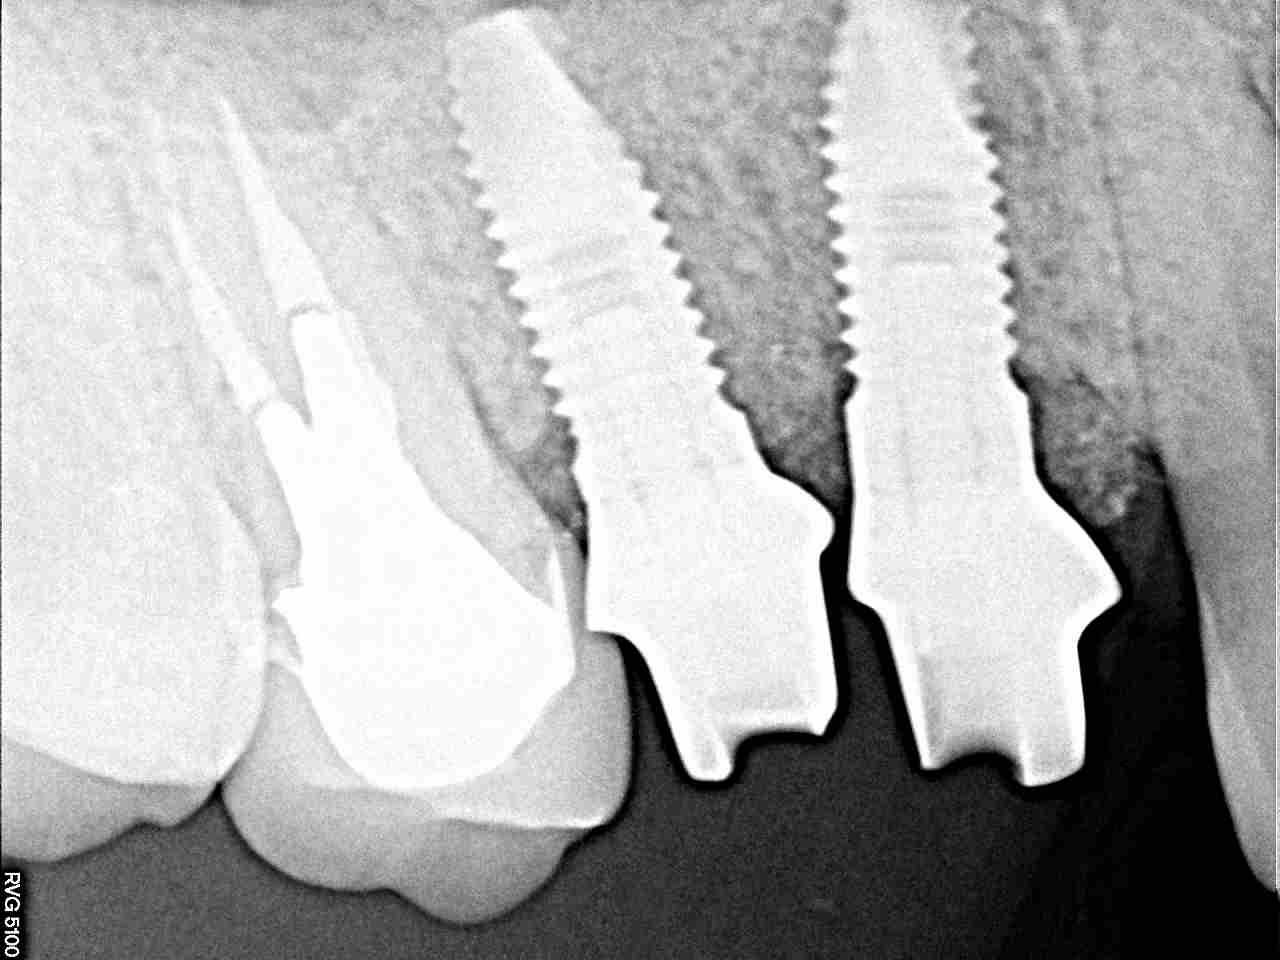

インプラントの最終補綴へ 埋入より3か月後になります|お知らせ |広島市安佐南区の歯科医院 インプラントの最終補綴へ 埋入より3か月後になります トップ お知らせ・ブログ お知らせ インプラントの最終補綴へ 埋入より3か月後になります インプラントの最終補綴へ 埋入より3か月後になります このように傷が治ります きれいに治っています カスタムアバットメントにて作成しています このように立ち上げています レントゲンにてもソーサライゼーションの起こりにくい埋入深さになります オールセラミックにて作成しています 抜歯窩にもドリリング時には足を取られ、上顎洞も持ち上げながら、 スペースが狭くなっていることもあり、5番は少し傾斜埋入となりました Web診療予約 初めての方へ 選ばれ続ける理由 院内設備について 歯が痛いしみる一般歯科 歯がぐらぐらする歯周病 健康な歯を保ちたい予防歯科 子供の虫歯予防をしたい小児歯科 銀歯をセラミックに審美歯科 白い歯を目指しませんか?ホワイトニング 矯正専門医がいるので安心矯正歯科 抜けた歯を補いたいインプラント・入れ歯 医院案内 スタッフ紹介 メリィハウス歯科クリニックオフィシャルホームページ ラベンダー歯科クリニックオフィシャルホームページ お知らせ・ブログ ホーム 診療科目 一般歯科 歯周病治療 予防治療 小児歯科 審美治療 ホワイトニング 矯正歯科 入れ歯・インプラント マウスピース矯正 初めての方へ 院長・スタッフ 設備紹介 医院案内・アクセス メニューを閉じる